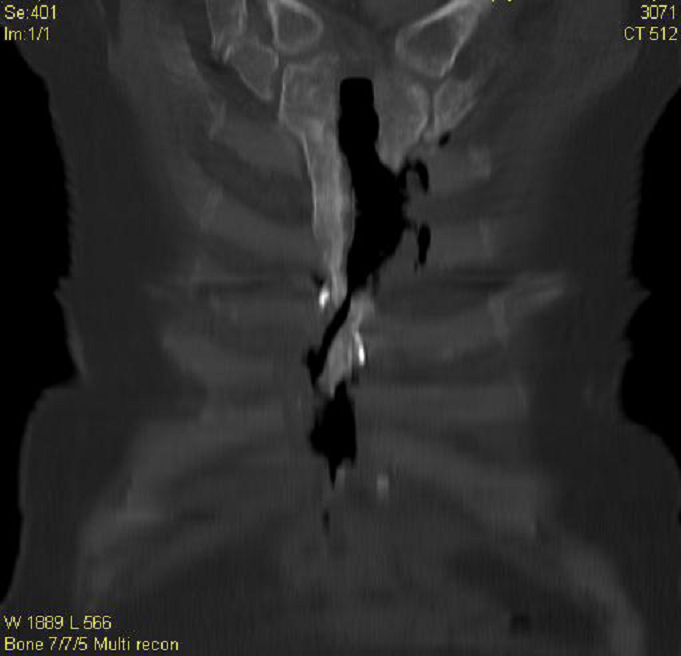

Diaqnostikası

Kliniki və instrumental (Rentgen, KT, MRT, fistuloqrafiya) müayinələr əsasında qoyulur.

MRT müayinəsi ətraf yumşaq toxumalarda olan dəyişikliyi və fistulanı dəqiq müəyyən edir. Fistuloqrafiya zamanı prosesin ölçüsü, fistula yolunun istiqaməti və sümük toxuması ilə əlaqəsi aşkarlanır.

Görüntüləmə əlamətləri nələrdir?

Sümüklərdə destruksiya, sekvestrlər

MRT – ətraf yumşaq toxumalarda olan dəyişiklik və fistulanı müəyyən edir.